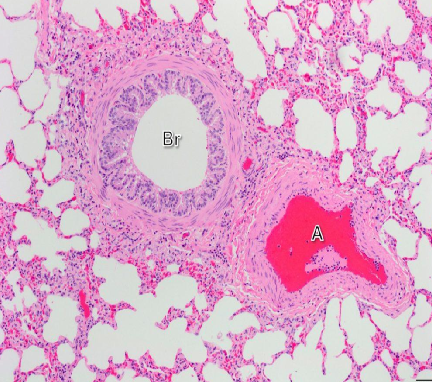

Section in the lung showing intrapulmonary bronchus

Bronchus

Intra pulmonary bronchus

1- epithelium, 2- smooth muscle, 3- cartilage

Section showing bronchiole and alveoli

Red = alveoli

Section showing bronchiole and alveoli (white spaces all around)

Red A = Artery

Bronchiole

Bronchus and Bronchiole